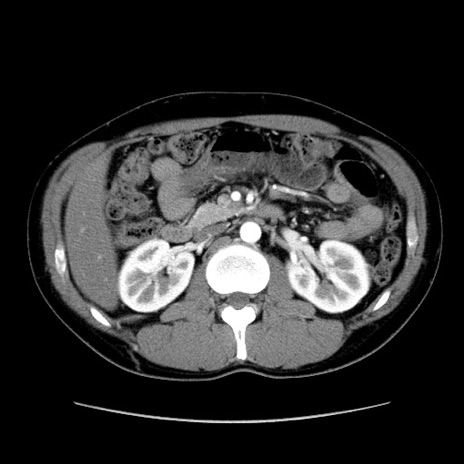

症例36(横断像)

【症例】20歳代 男性

【主訴】心窩部痛

【現病歴】今朝より上腹部痛あり。一旦軽快していたが再度出現したため救急要請。昨日夕に白身の魚を含む刺身を食べた。

【身体所見】BP 136/89mmHg、HR 74/min、BT 37.0℃、腹部:膨満、軟、心窩部に圧痛あり。反跳痛なし、筋性防御なし、腸雑音やや亢進あり。

【データ】WBC 17700、CRP 0.48